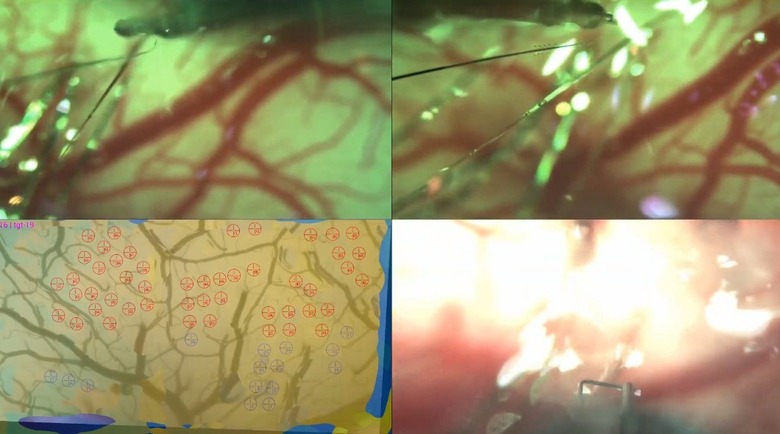

According to the article, its bundles of flexible threads are about one quarter the diameter of a human hair, implanted using needles to avoid blood vessels on the brain's surface. Then the embedded sensors capture information and send it to a receiver (the chip above) on the surface of the skull. From there it transmits wirelessly — Elon Musk said it could Bluetooth the information to your skull. Right now implantation requires drilling holes, but researchers hope in the future they can use lasers to avoid "unpleasant" vibration.

Neuralink president Max Hodak went on to explain why it's embedding sensors directly into the brain, near but not in neurons. Simply, it's the only way to send and receive the information necessary, from "spikes" of activity. A neurosurgeon is also part of the presentation, showing off some videos of the implantation technology, and how its robot can install thousands of wires directly into the brain while avoiding tissue damage and bleeding. Eventually, they'd like to do it without shaving the patient's head, although he acknowledged that the first operations will be more like current deep brain implants.